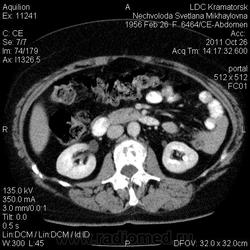

Здравствуйте! Вот уже месяц не могут поставить диагноз. Первичный очаг найти не удалось. Множественная миелома (несекретирующая?, т.к. по крови стерн. пункция не дает результата)?

Костное окно:

По имеющимся файлам-дайком я не нашла признаков опухоли. Имеется множественное остеолитическое поражение позвоночника, ребер, грудины, частично - таза. Лимфоузлы не увеличены. Тоже поставила бы на первое место миеломную болезнь. Диагностирование её не всегда простое дело. Поражена грудина и, наверное, нужно посоветоваться с онкологом (гематологом) стоит ли сделать стернальную пункцию.Советую написать в личку tatyana.